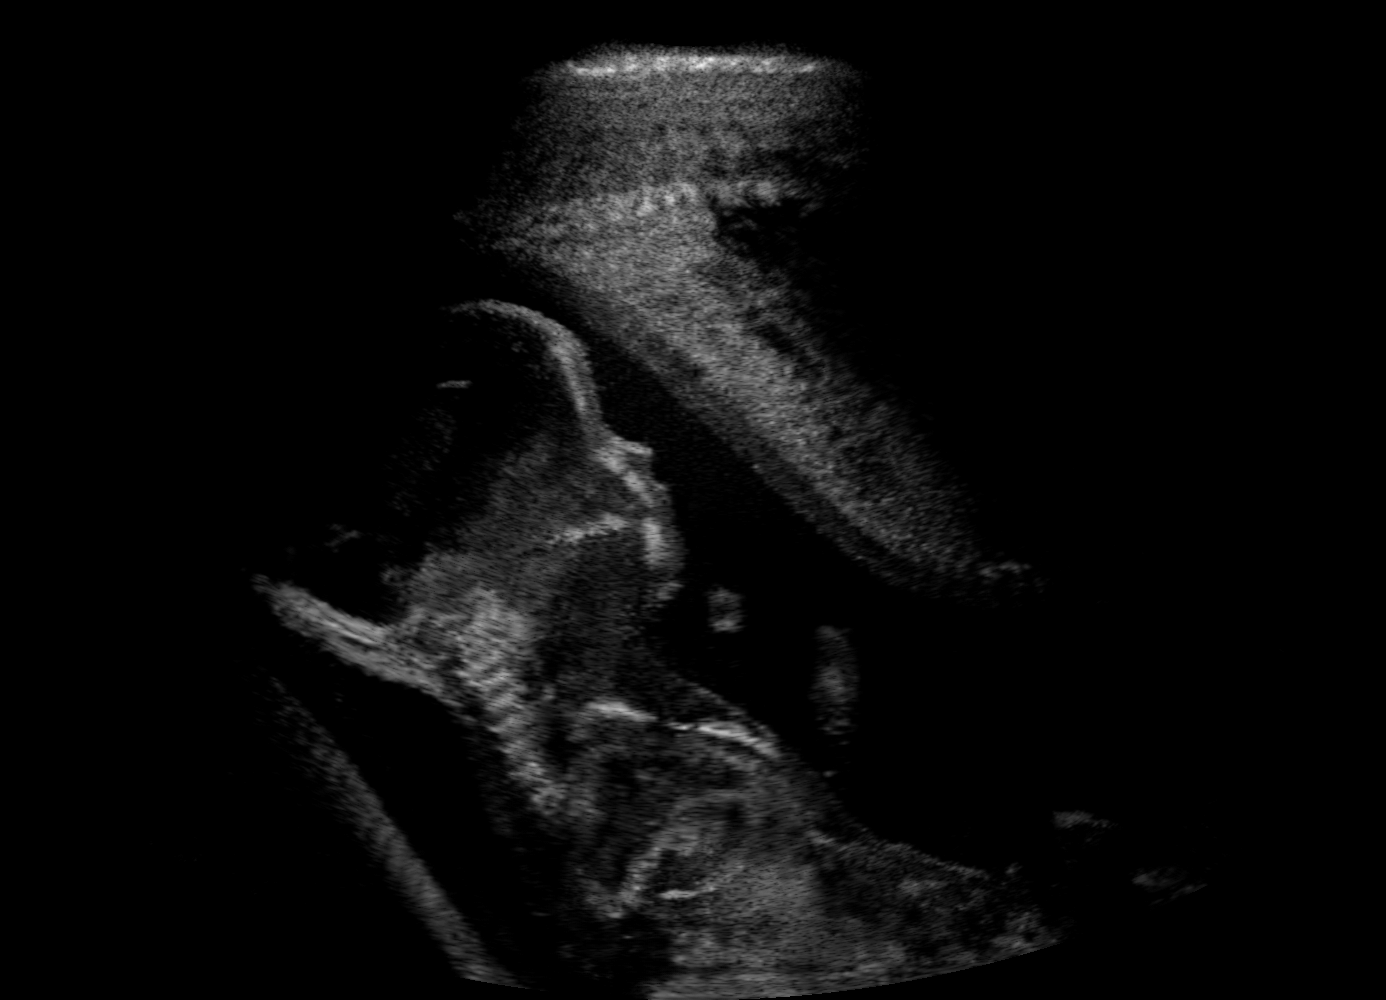

Qualitative evaluation.

Fig. 2 depicts the qualitative results for all the models mentioned above, with arrows pointing at structures relevant to discussion points below. The visual results of the ablated variants of SA2H show substantial quality degradation compared to the full SA2H model, demonstrating the importance of each proposed architectural contribution. Given only segmentation map in the network input, SA2H-att fails to generate acoustic shadows, e.g. those cast by the ribs. Detailed structures such as the cervical vertebrae are blurred out in the SA2H-concat results, which also contain hallucinated structures mainly due to insufficient preservation of input information along the encoding-decoding path. With SA2H-conv, checkerboard artefacts are observed due to the lack of proposed additional stride-1 convolutional layers. SA2H-noise without any explicit noise input is seen to be sub-optimal at generating textural details. The baseline method NSA2H fails to preserve anatomical structures and acoustic shadows in all cases, while the simulated textures also show significant artefacts such as checkerboard patterns. Realism of different simulation aspects may become relevant given different clinical applications and scenarios. For instance, improved structural preservation, e.g. with the hyperechoic bony structures such as the skull and the ribs, of the final model over its ablated variants and NSA2H may prove relevant in fetal head measurements, while the textural improvements facilitating screening fetal organ maturity, e.g. lungs. Compared to the silver-standard model LSA2H with a low-quality rendered image as additional input, SA2H is seen to be on par in structural preservation. Note that shadowing on homogenous regions (e.g. the rib shadowing on the homogenous lung region on the 4th column of Fig. 2) with our proposed method SA2H is represented more faithfully compared to LSA2H, whereas shadows on structurally complex regions (e.g. the skull shadowing around the heart and surrounding tissues on the 3rd column of Fig. 2) are suboptimal with our SA2H. Therefore, one may have to evaluate our method given particular simulation tasks, e.g. its clinical validity for fetal heart exams. However, even with low quality rendered images, LSA2H leads to artificial enhancements of intensities, lack of acoustic shadows, and low-quality textures especially near the probe, for which SA2H yields satisfactory results as illustrated in Fig. 2.

(a) Target

(b) SA2H

(c) SA2H-att

(d) SA2H-concat

(e) SA2H-conv

(f) SA2H-noise

(g) NSA2H

(h) LSA2H